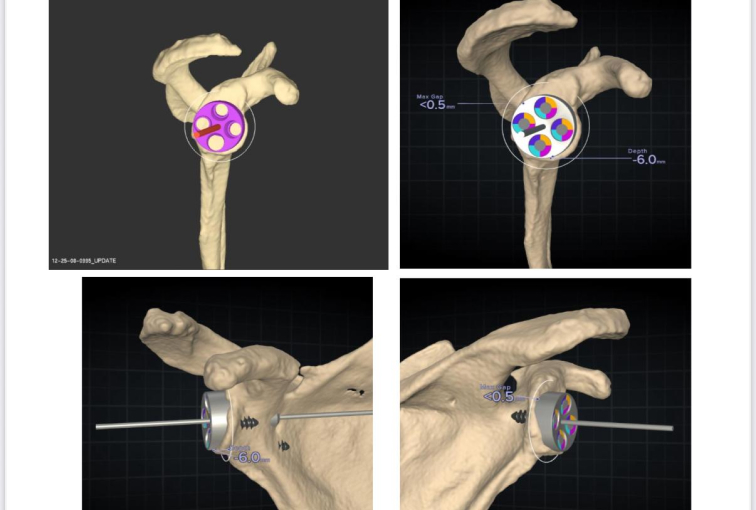

Seeking the blessings of His Holiness Jagadguru Dr. Sri Shivaratri Rajendra Mahaswami ji and offering our humble pranams to His Holiness Jagadguru Sri Shivarathri Deshikendra Mahaswami ji, JSS Hospital has achieved a historic milestone in healthcare. For the very first time in Mysuru, the Department of Orthopedics successfully performed a Reverse Total Shoulder Arthroplasty (RTSA) using state of the art Virtual Implant Positioning (VIP) technology by Arthrex.

Reverse Total Shoulder Arthroplasty is a sophisticated surgical solution designed for patients with severe shoulder dysfunction, particularly when conventional shoulder replacement proves ineffective. Individuals suffering from persistent pain, difficulty with daily activities such as combing hair or reaching the back, and pseudo-paralysis caused by rotator cuff insufficiency can benefit significantly from this approach. In this technique, the shoulder’s natural ball-and-socket orientation is reversed, where the glenoid socket becomes the humeral head and the humeral head assumes the role of the socket.

This modification empowers the deltoid muscle to compensate for damaged rotator cuff muscles, thereby restoring function and improving quality of life.

Initially reserved for irreparable cuff tear arthropathy, Reverse Shoulder Arthroplasty has now expanded in scope. It is increasingly considered for patients with primary osteoarthritis, complex proximal humeral fractures (especially Neer’s four-part fractures), and tumors. The decision to perform RSA takes into account patient-specific factors such as age, bone quality, activity levels, and the degree of rotator cuff compromise.